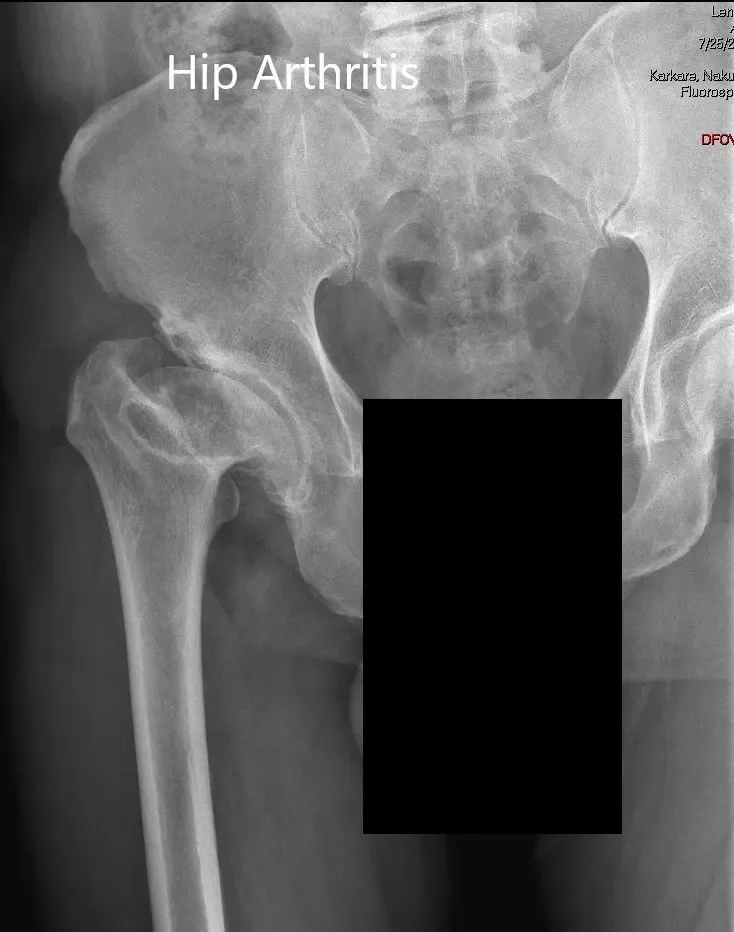

Preoperative X-ray showing the AP view of the pelvis with both hip joints

AP and lateral views of the right hip joint

Imaging revealed markedly deformed right femoral head and impacted the femoral neck. There were severe degenerative changes of the right hip.